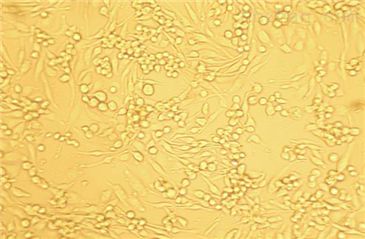

| 细胞名称 | MSTO-211H人肺癌细胞株 |

| 背景资料 | MSTO-211H细胞株是1985年从一位肺二相间皮瘤患者的胸水中建株的。这个病人接受过多种药物联合前期化疗。MSTO-211H细胞具有高亲和力的EGF结合位点,并表达神经元特异性烯醇酶(NSE)及人绒毛膜促性腺激素(HCG)的α与β亚基。未检测到左旋多巴胺脱羧酶(DDC),邦巴辛与神经tensin。细胞过表达c-myc原癌基因,并没有观察到基因重排或扩增。V-src、v-abl、v-erb B、c-raf 1、Ha-ras、Ki-ras和N-ras的表达呈阳性。未检测到N-myc、L-myc、c-myb、c-fos、v-fes、v-fms 和 v-sis癌基因的表达。这株细胞的饱和浓度能达到每平方厘米400000,但达到这个浓度时就会从表面脱落。 |

| 细胞形态 | 贴壁;成纤维细胞样 |